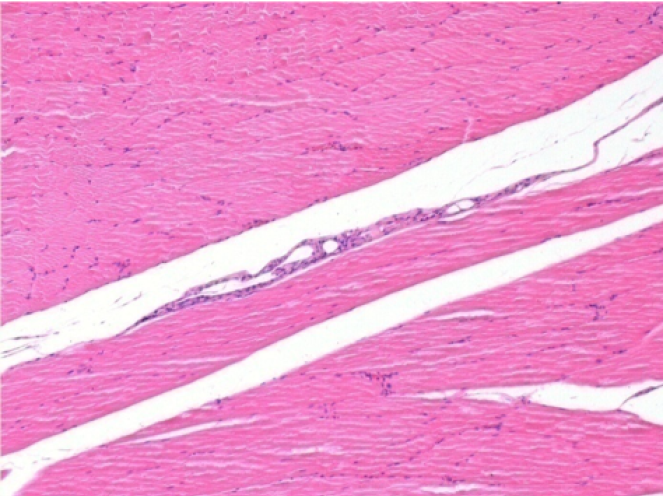

Через 1 місяць після ін'єкції Ендопілу 0,1 мл у правий претибіальний м'яз.

Те, що видно на знімках чорним кольором, не є некрозом, як можуть собі уявити деякі науковці!

Насправді, слід взяти до уваги 4 висновки